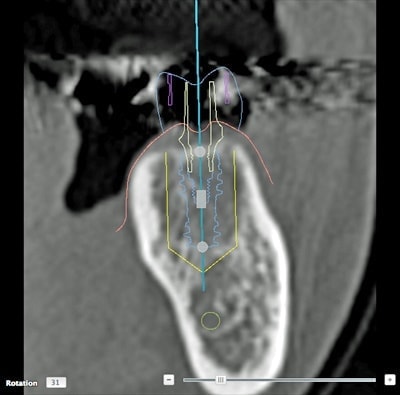

CTによる詳細な現状把握

レントゲンでは把握できないことまでCTでは確認することが出来ます。

身体を断面や立体図として見ることが出来、骨はもちろんの事、神経や血管に至るまで確認することができます。

そのデータを元に、どのような角度、どのような深さでインプラントを打ち込むかなど、的確な治療計画を立てることができます。

CT・診断:5,000円(税別)※インプラント治療を受ける場合は無料